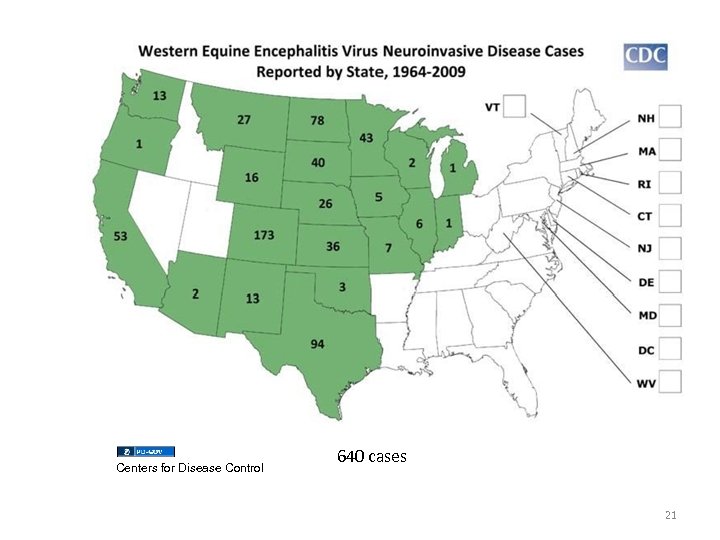

Centers for Disease Control 640 cases 21